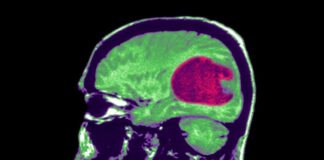

Harvard: “Yapay zeka beyin tümörü tedavisine yardımcı olabilir; Kanseri̇ çözmek için...

Harvard: "Yapay zeka beyin tümörü tedavisine yardımcı olabilir; Kanseri̇ çözmek için de ona İhtiyacımız var"

Yapay Zeka, en yaygın beyin tümörü olan gliomaların analizine yardımcı...